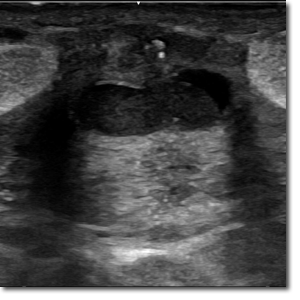

Adolescente de 13 años que acude a Urgencias por dolor en la mama derecha de una semana de evolución. Afebril. Niega telorrea, traumatismo previo o menstruación actual. No presenta antecedentes personales de interés, pero sí antecedentes familiares de cáncer de mama en madre y abuela materna.